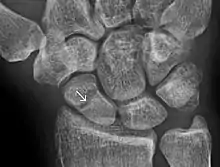

A subtle scaphoid fracture